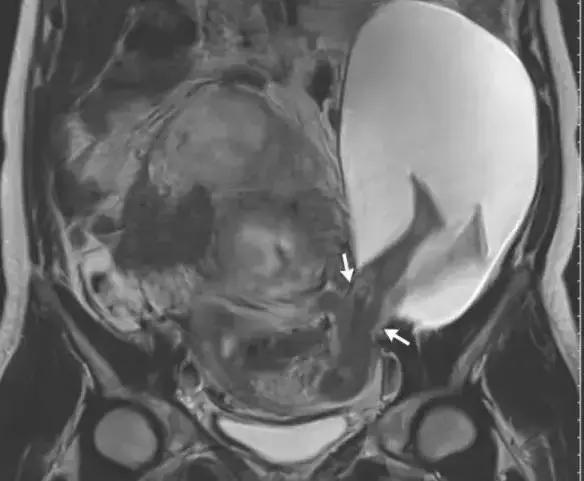

该名妈妈的磁共振扫描(MRI)照片可以看到,箭头所指之处就是宝宝的双脚,而子宫壁处在怀孕初期已有2.5cm大的撕裂,使得部分装着发育中宝宝的羊膜囊露出子宫,宝宝也因为胎动刚好把脚伸出去,造成惊人的景象。

医生表示,通常子宫壁撕裂对导致疼痛与出血,但宝宝的脚伸出去刚好可以帮忙止血,当时发现时,子宫壁已经增加撕裂到5cm,宝宝的双脚跟腹部都已经在子宫外,随即进行剖腹生产,所幸母子均安。